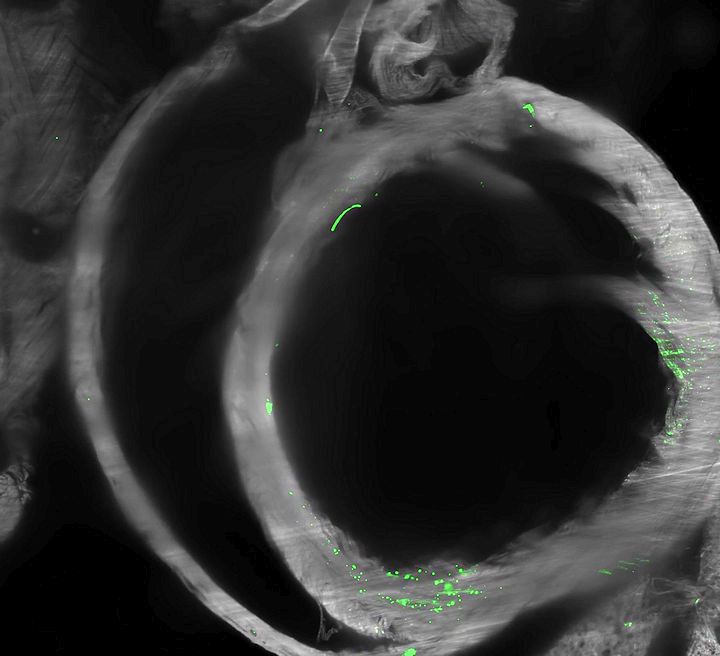

Zöld fluoreszcens fehérje (EGFP) expresszió egér szívében 72 órával kis adag, lipid nanorészecskékbe csomagolt EGFP mRNS-injekció beadása után

4. ábra: Lipid nanorészecskékkel bejuttatott mRNS-ből származó fehérje expressziója. Teljes test (a), lép (b), máj (c) és szív (d). f: az izomba beadott, lipid nanorészecskékkel bejuttatott mRNS-ből származó SARS-CoV-2 S1 tüskefehérje eloszlása a testben 72 órával az injekció beadása után. Tüskefehérjék a szívben (f′).

Luo, J., Molbay, M., Chen, Y. et al. Nanocarrier imaging at single-cell resolution across entire mouse bodies with deep learning. Nat Biotechnol (2025). https://doi.org/10.1038/s41587-024-02528-1. CC BY 4.0